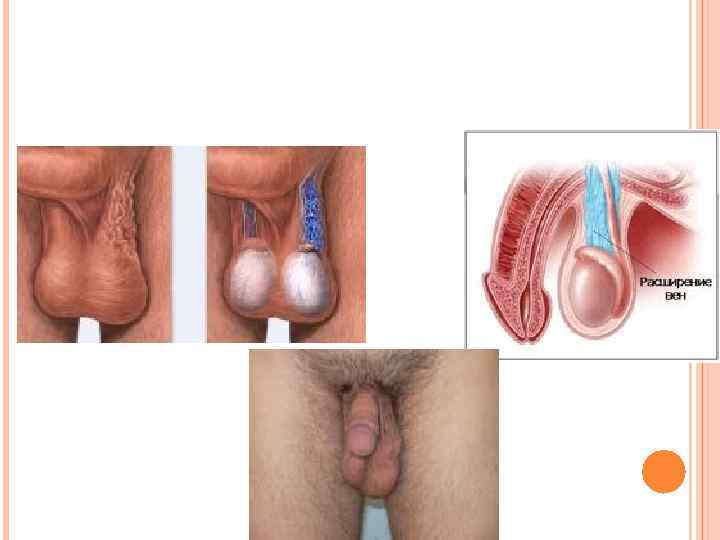

Варикоцеле – варикозное расширение вен семенного канатика «Аорто-мезентериальный пинцет»

Варикоцеле – варикозное расширение вен семенного канатика «Аорто-мезентериальный пинцет»